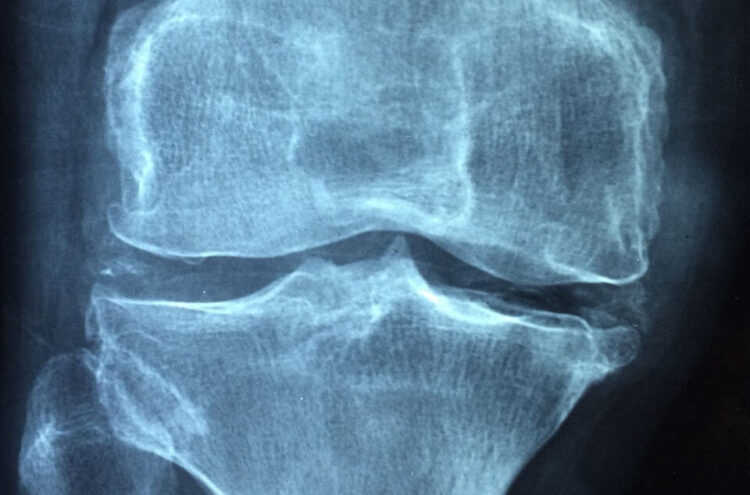

È stata scoperta una piccola proteina (un peptide) che potrebbe rivoluzionare le terapie per l’osteoporosi. Questo ‘osteopeptide’ endogeno, soprannominato “Pepitem”, svolge una duplice funzione: ferma il riassorbimento e la perdita ossea e favorisce la formazione di nuovo osso sano.

Uno studio condotto su animali, pubblicato sulla rivista Cell Reports Medicine , ha mostrato che Pepitem ha garantito la formazione di nuovo osso sano in topolini con problemi di osteoporosi. La ricerca è stata coordinata da Helen McGettrick dell’Università di Birmingham.

Pepitem potrebbe assumere un ruolo centrale nella lotta all’osteoporosi perché stimola la formazione di nuovo osso dall’interno, sfruttando i meccanismi fisiologici endogeni.